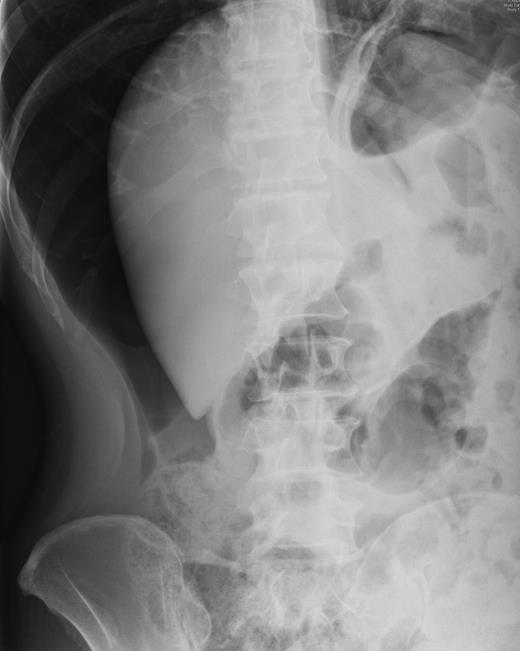

He was taken for urgent laparotomy to evacuate the free gas and aid diagnosis. The bowel was extensively examined and no evidence of perforation was found. The abdominal wall was closed and he returned to the ward. Subsequent X-rays showed that the pneumoperitoneum had resolved. Post-operatively his CRP level was 226 and he went into ileus requiring nasogastric tube placement (Fig. 3). With recurrence of normal bowel activity and with settling of his symptoms, he was discharged.